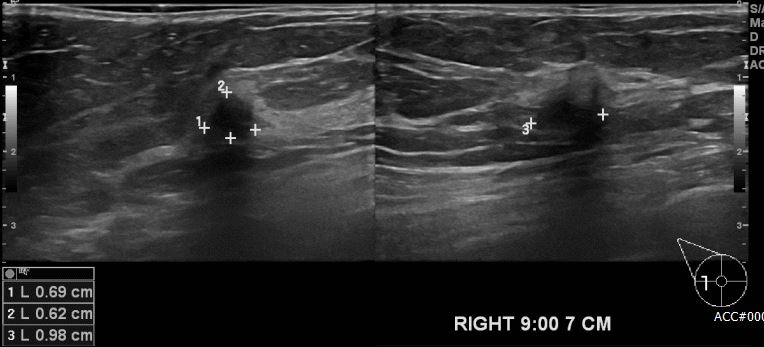

상기환자  우측 유방의 멍울로 내원하신 60대 여성분으로 우측 9시 방향에서 7cm

떨어진 거리의 멍울 조직검사 시행하여 우측 침윤성 유관암 진단 되었습니다.